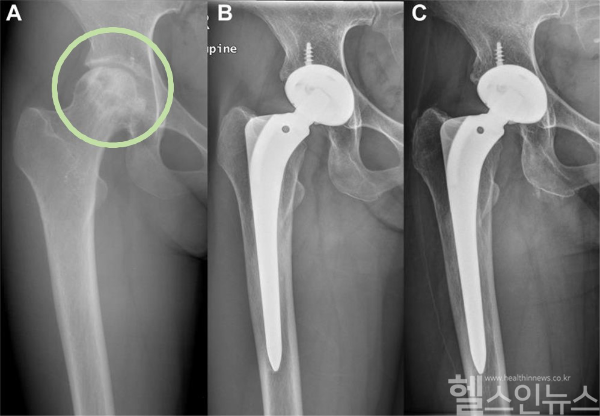

김홍석, 유정준 서울대병원 정형외과 교수팀이 1997년 11월부터 1998년 4월까지 3세대 세라믹-세라믹 관절면 인공고관절 전치환술을 받은 57명을 25년 이상 추적하여 이 수술의 장기적 안정성과 기능적 성과를 입증한 결과를 13일 발표했다고 밝혔다.

영상 분석 결과, 주요 합병증인 인공관절 주변부 골용해(관절면 마모 및 감염 등으로 인하여 뼈 조직이 파괴되는 현상) 및 인공관절 해리(뼈와 인공관절이 분리되는 현상)도 발견되지 않았다.